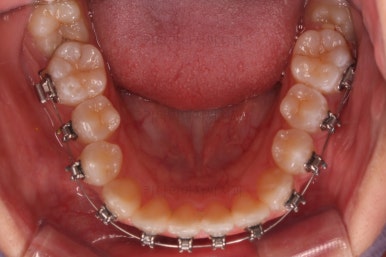

이번에 사용한 장치는 엠파워메탈이라고 하는 자가결찰(철사를 잡아주는 뚜껑이 달려있는) 메탈(금속성분) 장치입니다.

매우 장점이 많으나 심미성과 재료 제작비용 때문에 상대적으로 저렴한(이것도 장점일 수 있죠) 장치입니다.

쓰러져 있던 치아도 장치를 부착하여 일으켜 세워주는 힘을 줍니다.

자칫 나머지 치열이 틀어질 수 있기 때문에 아랫니에는 부산교정 미니스크류를 이용해서 반작용을 막아줍니다.

점점 뒤쪽 치아가 바로 일으켜세워지고 있네요.